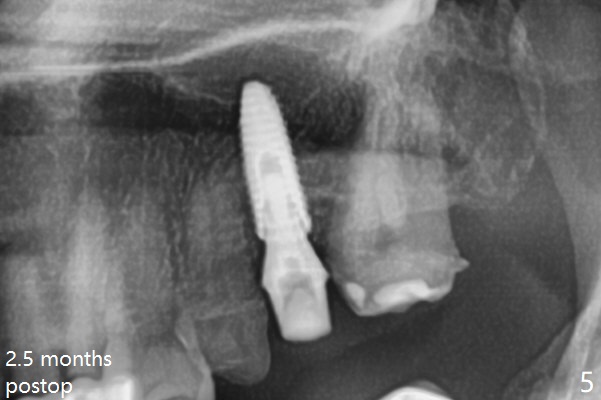

#13-15 FPD has not been used properly because of discomfort for 2 years. Before its removal, the discomfort derives from probing of the distal of #13 and mesial of #15, corresponding to calculus in the proximal areas. SRP is performed in UL quadrant after FPD removal. Bone density at the crest of the edentulous area is normal, while that of the medulla is low. After determination of trajectory and depth of initial osteotomy (Fig.1 (5 mm straight incision)), the site is underprep for a 4.5x13 mm Implant. Following adjustment, the implant is placed slightly subcrestal (Fig.2,3). It is possible that the discomfort of the previous FPD is due to overload, as suggested by the prominent buccal plate at #13 and 15, as compared to that of #12 (Fig.4 (5.2x4.5(3) mm cementation abutment at #14). Postop follow up shows that the tooth #15 may need RCT. The implant seems to enter the sinus (Fig.5 (2.5 months postop)) and be ready for restoration 3.5 months postop (Fig.6).